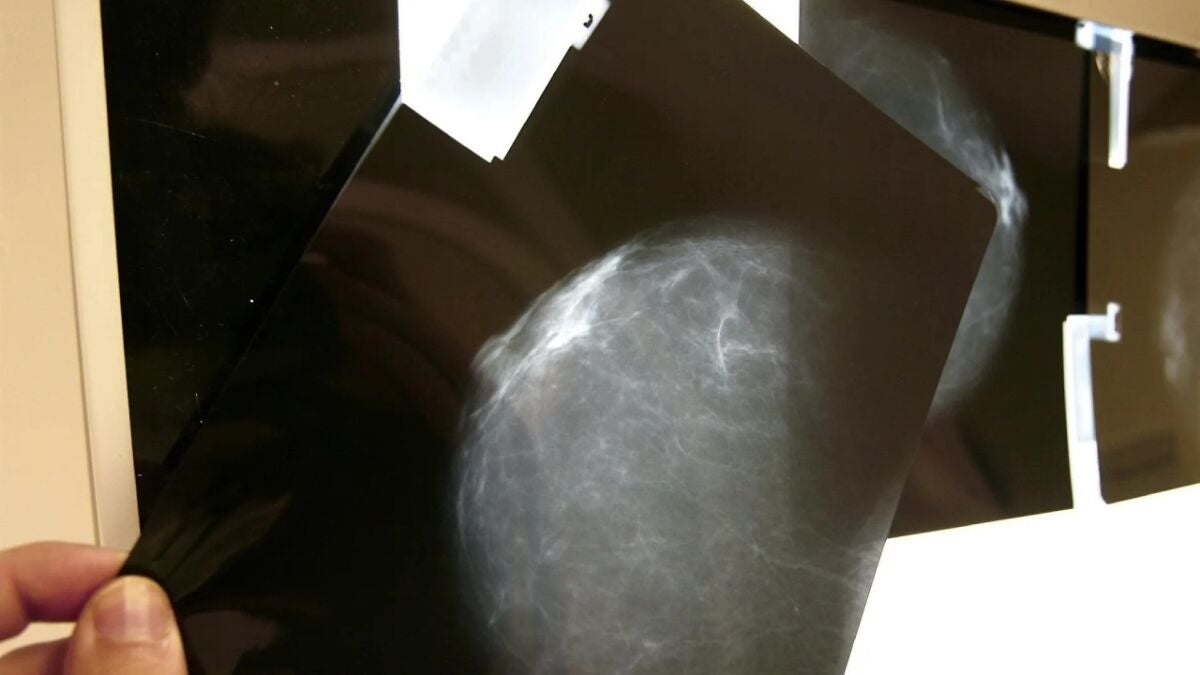

El cáncer de mama triple-negativo es uno de los canceres más agresivos que existen. Ahora han identificado una molécula con resultados "prometedores" en la investigación para este tipo de cáncer.

Investigadores del Instituto de Investigación Biomédica de Málaga (IBIMA Plataforma Bionand) han identificado una molécula para tratar el cáncer de mama triple negativo, uno de los más agresivos, conocido por su resistencia a las terapias convencionales y su tendencia a la rápida propagación.